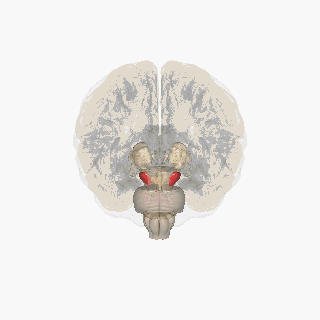

Substantia nigra

![]() Substantia nigra highlighted in red. | |